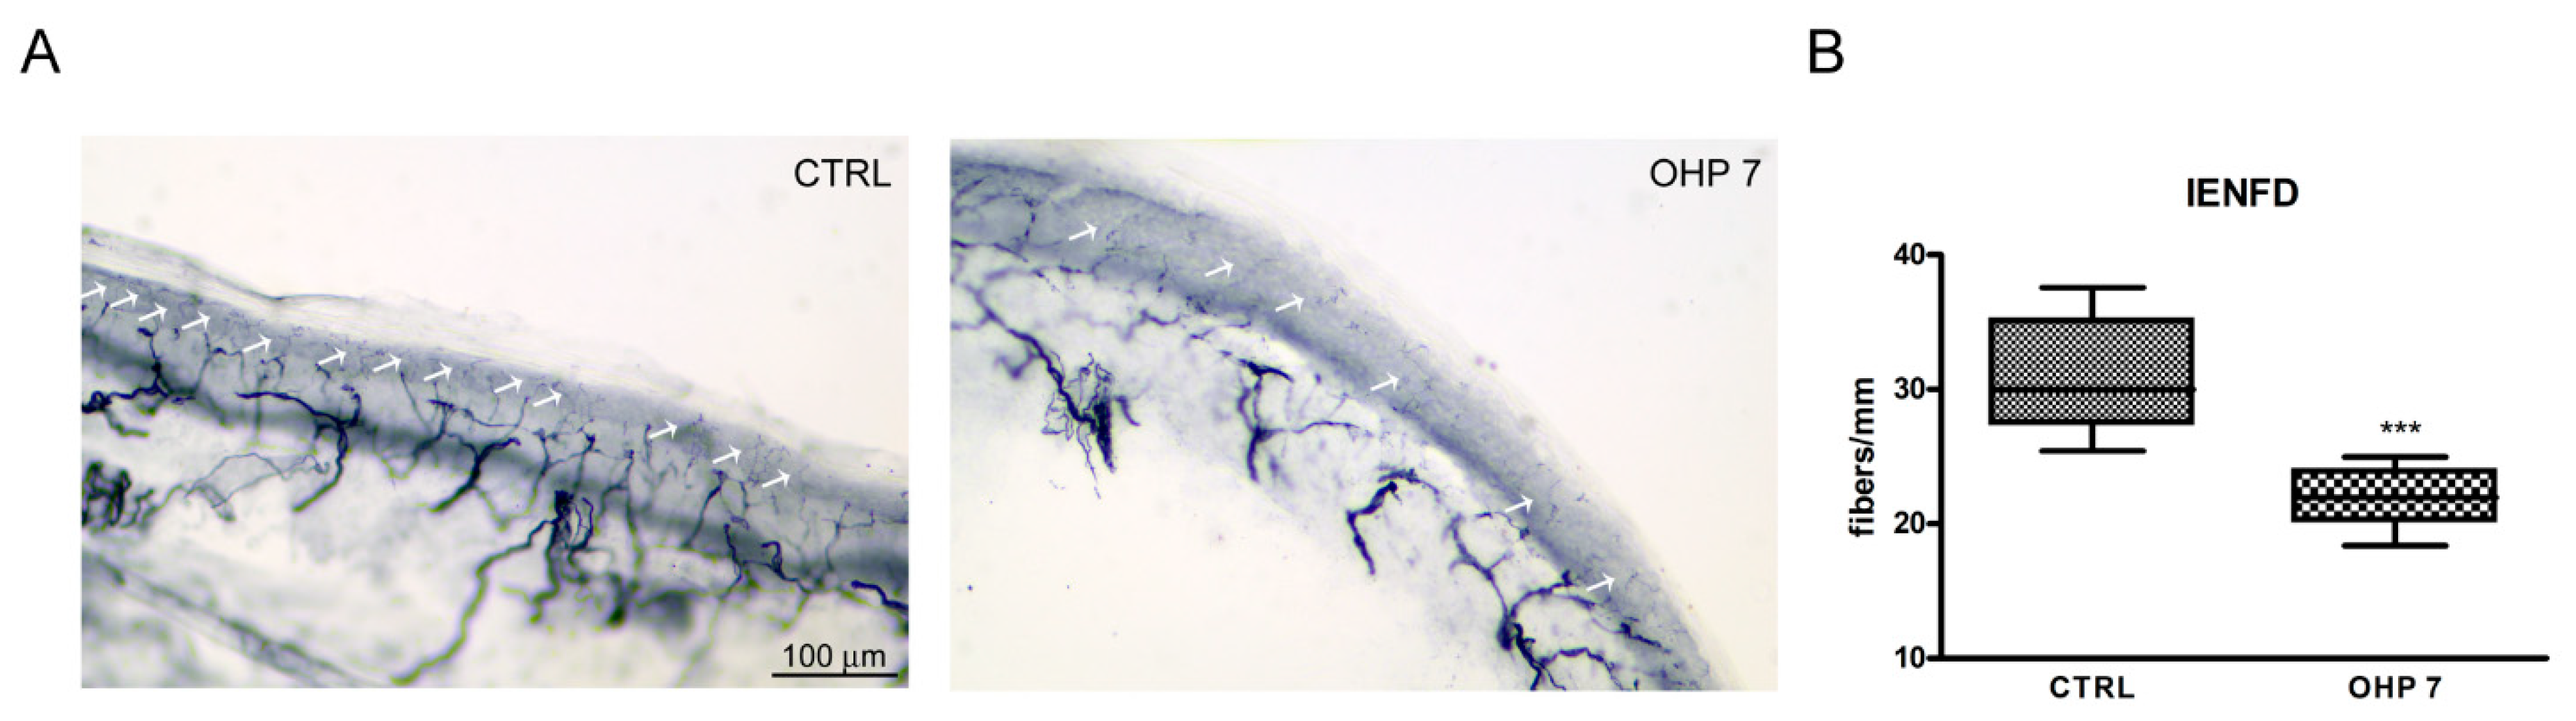

2.2.4. Intraepidermal Nerve Fiber Density (IENFD)